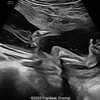

A 33-year-old nullipara with non-contributory medical history presented at 20 weeks, 6 days based on an early scan. Ultrasound revealed the following findings. There were no other apparent abnormalities. What is the most probable diagnosis?